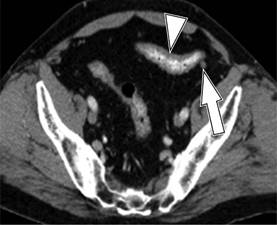

El estadio de la enfermedad en pacientes con diverticulitis a menudo se determina mediante el sistema de clasificación de Hinchey modificada por Wasvary (1999) y los hallazgos tomográficos por Kaiser a los que se incorporan los resultados de imagen (Cuadro 1 y Figura 1),16 los cuales comprenden desde el estadio 0 hasta el IV, en los que el estadio 0 (Figura 2) nos habla de una diverticulitis clínicamente moderada. El estadio I se divide en dos el IA (Figura 3) que se refiere a la inflamación pericólica limitada sin absceso y el estadio IB (Figura 4) en el que además de inflamación hay absceso adyacente a la zona de inflamación. En el estadio II (Figura 5) se encuentra el absceso pélvico, retroperitoneal o a distancia. En el estadio III (Figura 6) evoluciona a peritonitis generalizada sin comunicación a la luz intestinal y en el estadio IV hay peritonitis fecaloide con comunicación a la luz intestinal.17,18

Figura 3: Diverticulitis grado IA: TC con contraste en corte axial muestra engrosamiento de la pared del colon descendente (flecha) y cambios en la grasa pericólica (cabeza de flecha).